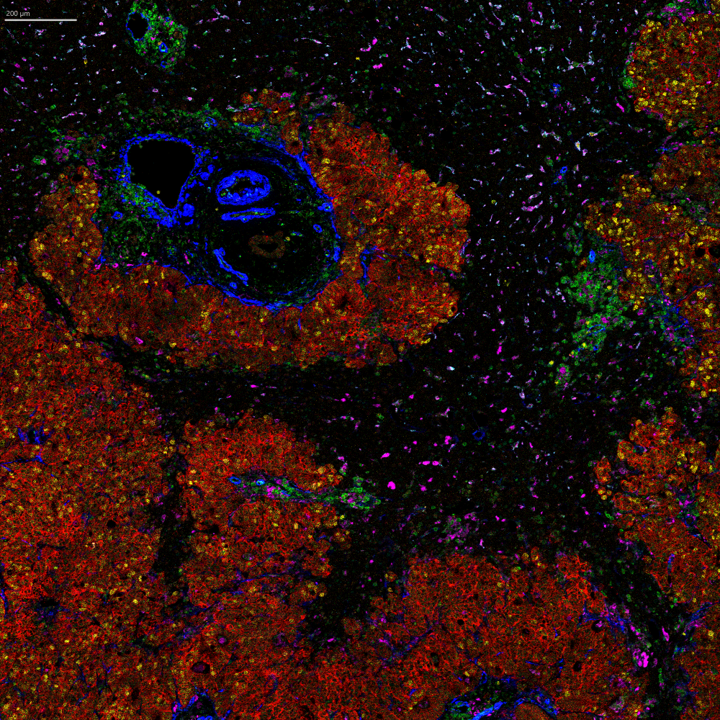

IMC platforms enable the comparison of spatial transcriptomic data with a choice of up to 45 spatial proteomic markers in the same section. This image shows six of 43 markers detected in the same scan.

Image of clear cell renal cell carcinoma tissue